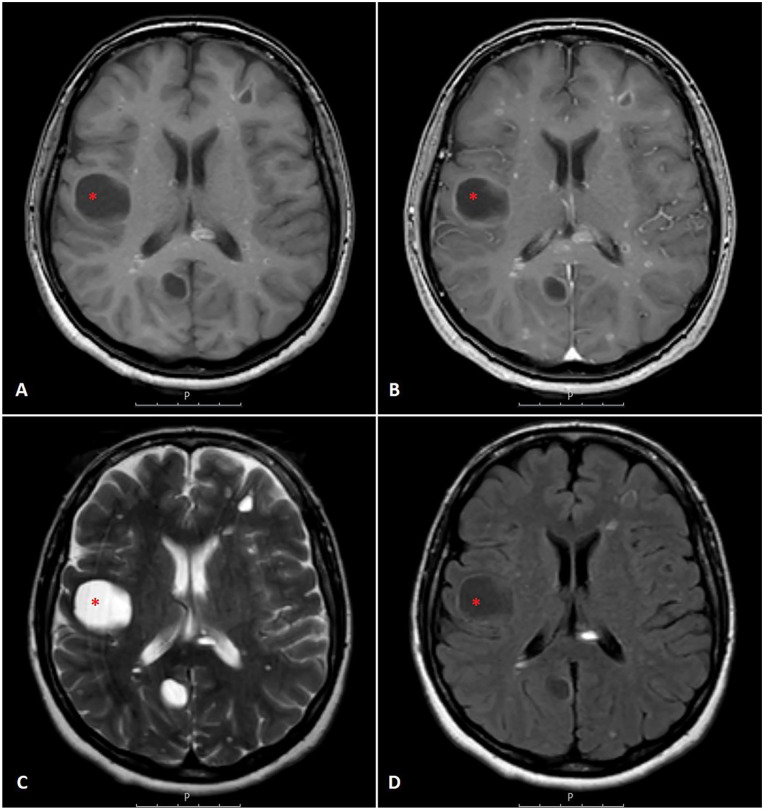

肺神经内分泌肿瘤包括神经内分泌癌和神经内分泌肿瘤(NETs)。net也被称为类癌(CaTs),分为典型类癌和非典型类癌(AC)。肺部cat常转移到不同部位,包括局部淋巴结、肺、肝和骨;然而,转移到大脑是相对罕见的。早期出现脑转移的患者更是罕见。我们报告一例50岁的女性患者,她最初表现为神经系统症状和磁共振成像结果提示多发性硬化症。尽管最初的治疗是多发性硬化症,但进一步的评估发现了一个罕见的支气管肺AC肿瘤转移到脑部的病例。本病例强调了在出现非典型神经症状的患者中考虑转移性疾病的重要性,特别是当初始治疗未能产生预期结果时。我们的文献回顾显示了7例最初表现为脑转移的cat,我们的患者是所有已发表病例中最年轻的。

Neuroendocrine neoplasms of the lung include neuroendocrine carcinomas and neuroendocrine tumors (NETs). NETs are also known as carcinoid tumors (CaTs), which are categorized as typical carcinoid and atypical carcinoid (AC). Pulmonary CaTs often metastasize to various sites, including regional lymph nodes, lungs, liver, and bone; however, metastasis to the brain is relatively rare. It is even rarer for patients with CaTs to present with signs of brain metastasis initially. We report the case of a 50-year-old female patient who initially presented with neurological symptoms and magnetic resonance imaging findings suggestive of multiple sclerosis. Despite initial treatment for multiple sclerosis, further evaluation uncovered a rare case of bronchopulmonary AC tumor metastasis to the brain. This case highlights the importance of considering metastatic disease in patients presenting with atypical neurological symptoms, especially when initial management fails to yield expected outcomes. Our literature review revealed 7 cases of CaTs initially presenting with brain metastases, with our patient being the youngest among all published cases.